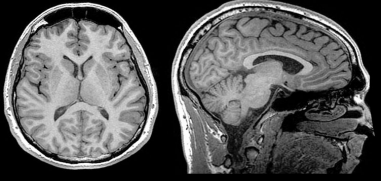

Structural MRI (sMRI)

This basic technology (the same as many have experienced in a medical setting) can be varied to allow various specialized forms of imaging. The most basic application for intelligence research is structural MRI, or sMRI. This is essentially a snapshot of the brain, but the image is 3D. It can be rotated and viewed from any angle and can produce a “slice” image of the brain at any depth. Since the image is in 3D, the points are also 3D, unlike the 2D pixels of a digital photograph. The 3D representations are known as voxels.

One of the problems encountered in understanding a brain image is that brains are not identical in size and shape. Yes, they are all generally the same in appearance, just as our faces are similar yet different enough that we can recognize them. A researcher must be able to compare brains, despite their differences. This can be accomplished by a computer using a process known as voxel-based morphometry. The process morphs the MRI data to fit a standard form and smooths the results so that they can be analyzed. For example, an area of great interest is cortical thickness. In order to study it and to compare different brains, the cortex representation has to be smoothed so that the folds are removed and the resulting artificial image retains the dimensions that are of interest, while losing the irregularities that would otherwise make it unmanageable.

Above: Left image (axial view) and right image (sagittal view) of structural MRI

The cortex contains cortical columns that are vertical structures of variable length and composition. The number of these columns is related to cortical surface area, while their length is a function of cortical thickness. Their relation to intelligence is known primarily by the correlations found in average and local measurements of cortical thickness and in cortical surface area. A good bit of study of cortical thickness (CT) has been related to the NIH (National Institute of Health), e.g., the Study of Normal Brain Development.

One finding is that cortical thickness increases in early childhood, then begins a slow decrease around ages 7 to 10 years. When plotted against time, the trajectories of bright children (from longitudinal NIH data) show greater thickness at every age than for less bright children. During the first phase, thickness increases more rapidly in bright children, but exhibits a similar rate of thinning following the peak. This has obviously important significance in the verification of the high heritability of intelligence; the trajectories are set from early childhood. The strongest correlations between CT and IQ are found in the age range of 8 to 12 years.